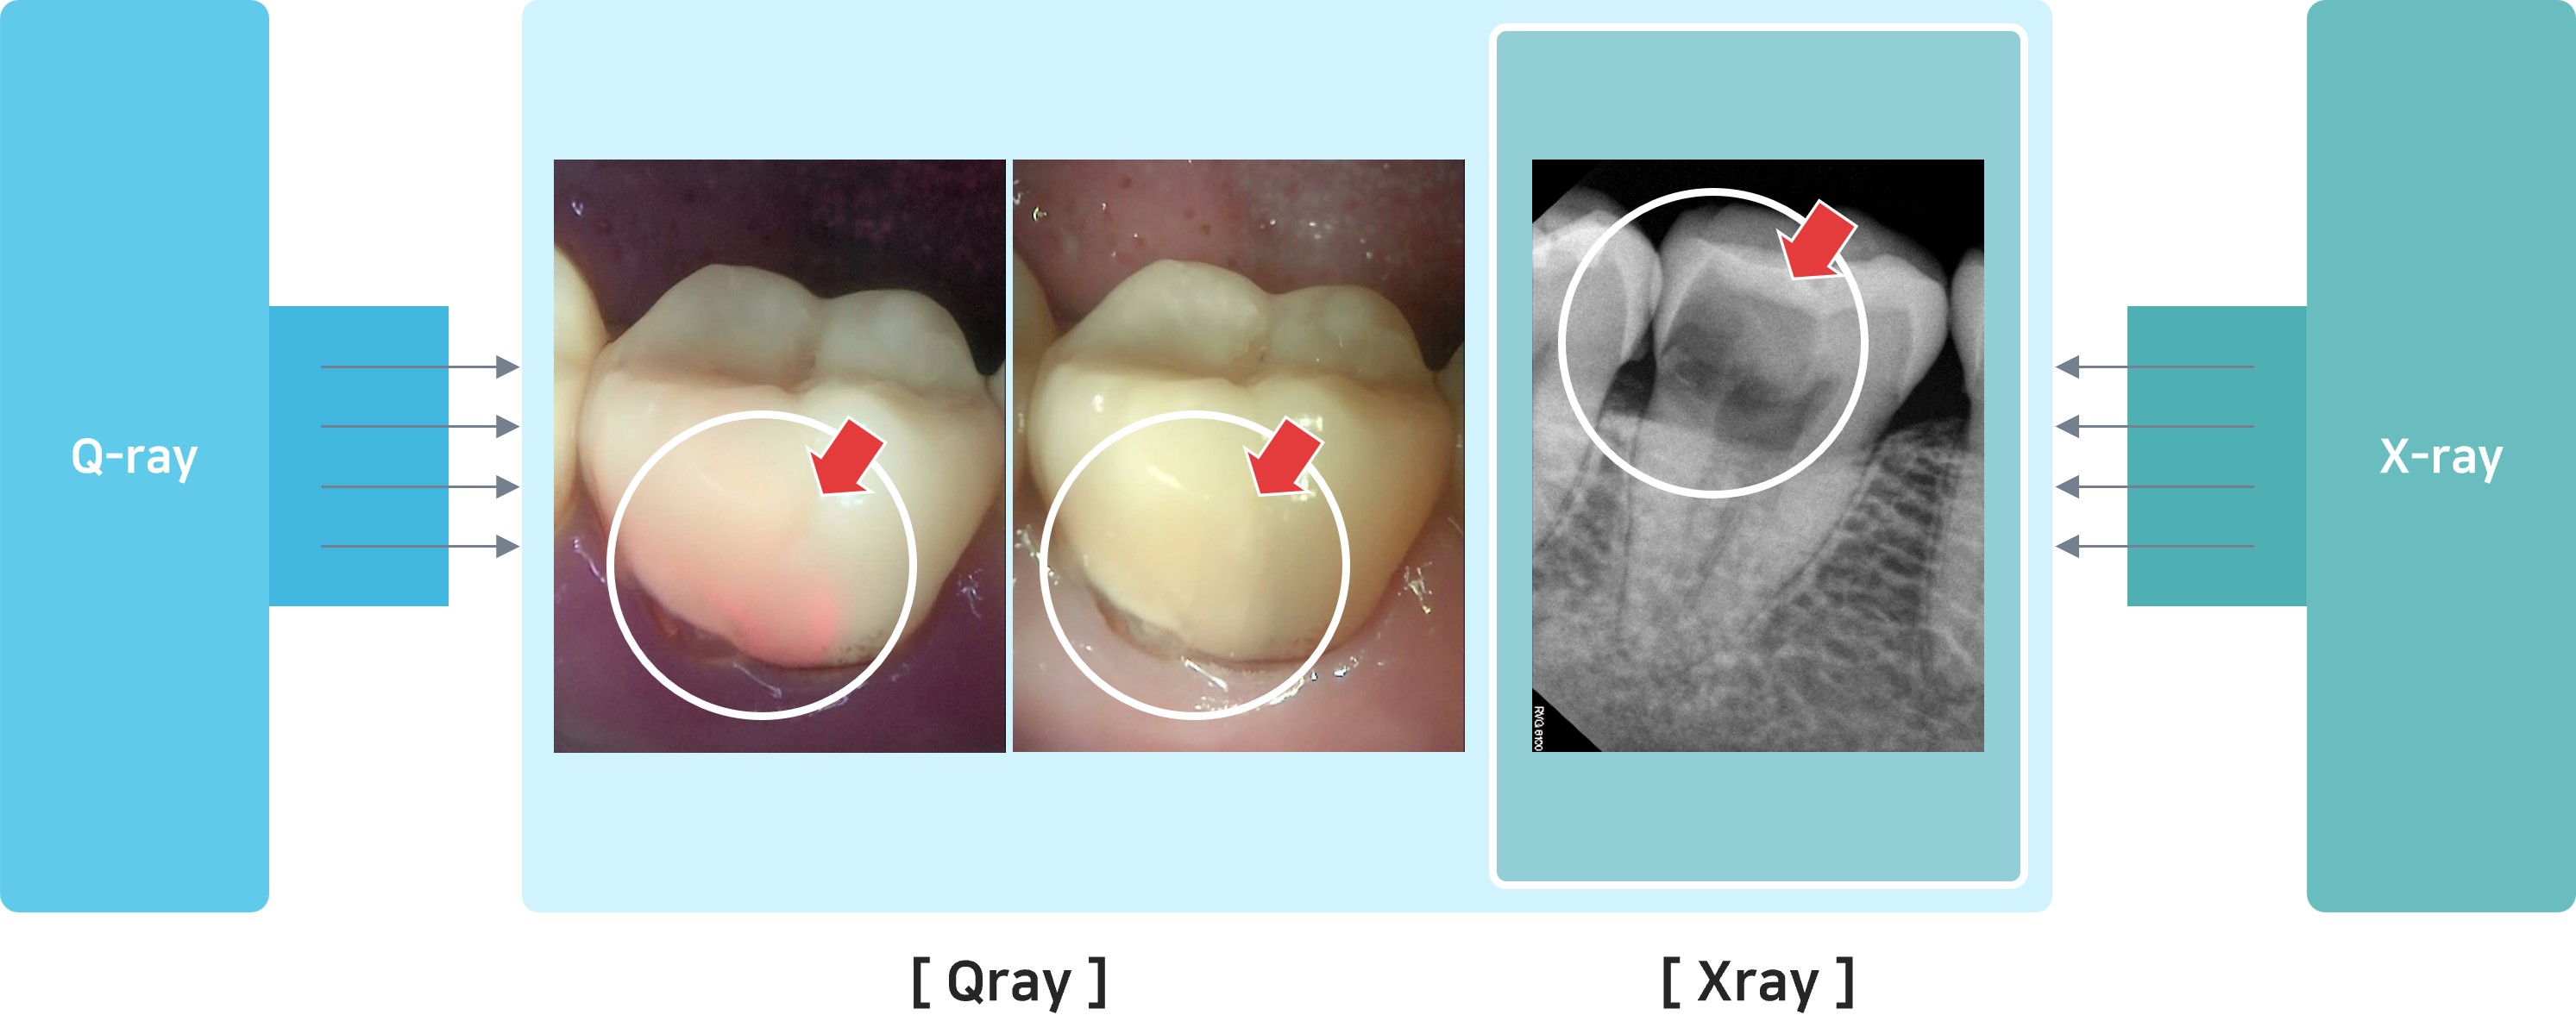

☞☞ 치과를 가시면 원장님들이 시진이라고 눈으로 입안을 검사하는 과정이 있습니다. 그 전에 큐레이라는 형광검사와 방사선검사를 시행하면 치아외부의 상태는 큐레이 사진이 보여주고, 파괴된 상태는 방사선 사진이 보여주게 됩니다. 보는 것이 믿는 것입니다. 치과에서 미래를 준비하시려면 '붉은형광, 큐레이' 입니다.

당사는 정량광형광검사(QLF™: Quantitative Light-induced Fluorescence) 기술을 기반으로 입안에 있는 치태, 치석, 치아우식증, 치아균열 등과 같은 구강질환을 진단검사하는 큐레이 장비를 개발, 판매하는 사업을 영위하고 있습니다. 본 검사법은 2018년 8월에 신의료기술 평가를 완료하고 2021년 6월부터 치과진단검사법으로 국민건강보험 요양급여 항목에 포함되어 국내 치과병의원에서 진료과정에 적용을 확대하고 있습니다.